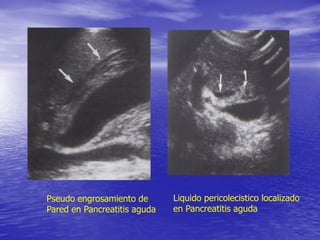

INFLAMACION O PERFORACION

DE ORGANOS VECINOS

• ULCERA DUODENAL PERFORADA

• PANCREATITIS

• DIVERTICULITIS O PERFORACION EN

FLEXURA HEPATICA DEL COLON

Pseudo engrosamiento de

Pared en Pancreatitis aguda

Liquido pericolecistico localizado

en Pancreatitis aguda